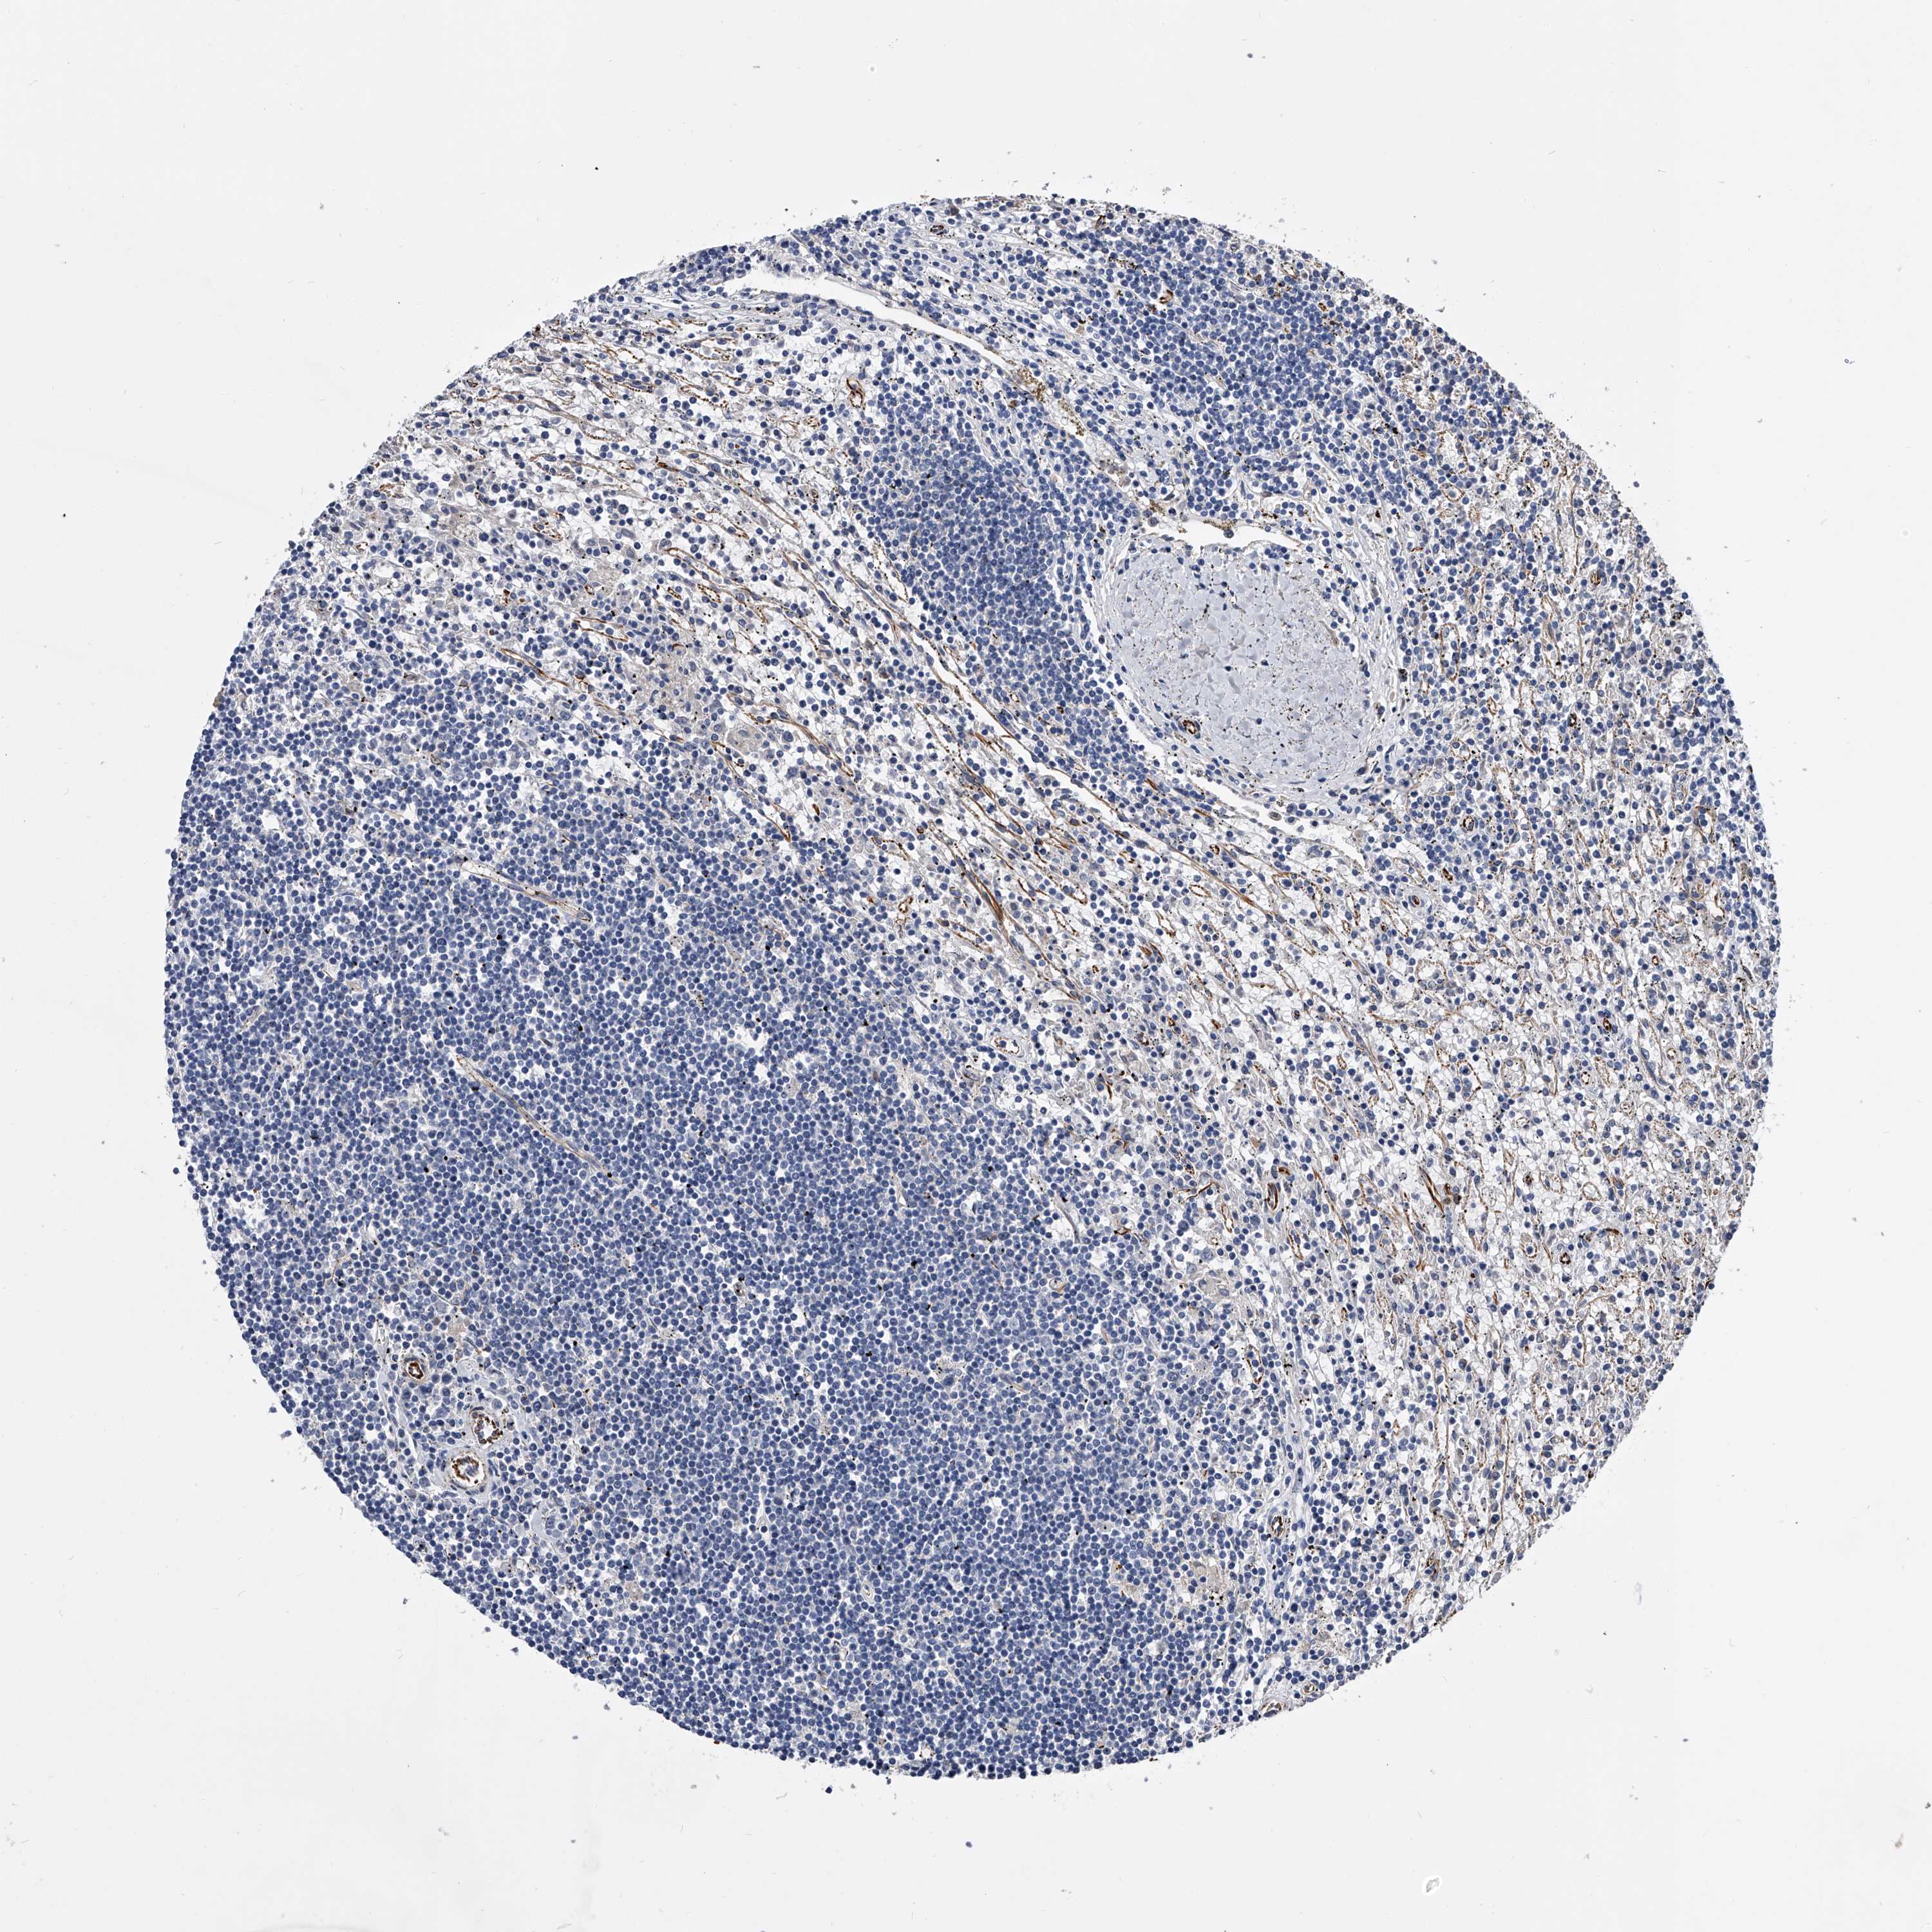

LYMPHOMA